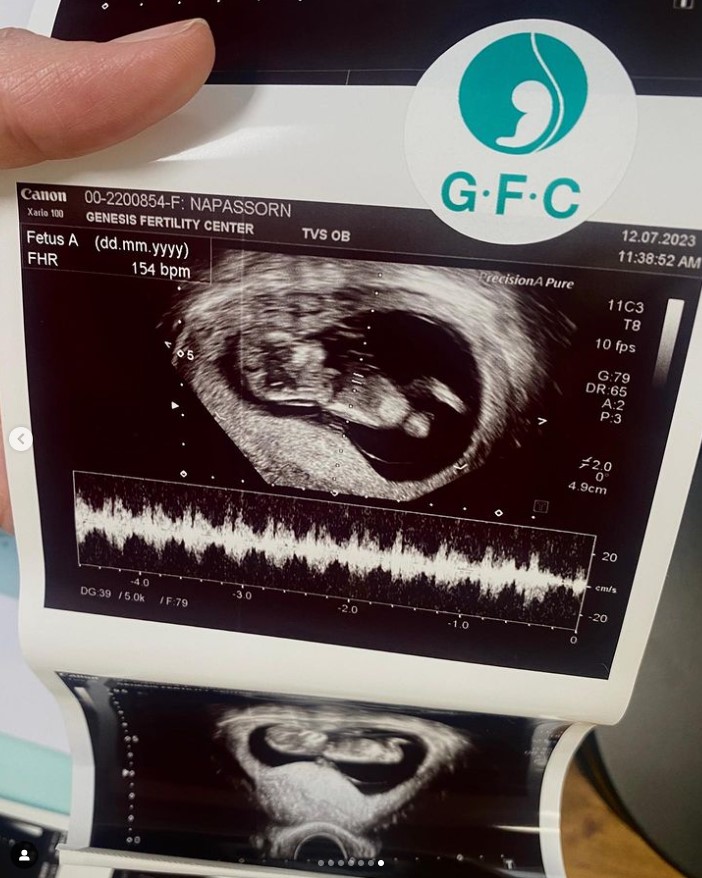

ล่าสุด 24 กรกฎาคม 2566 นิว นภัสสร ได้ประกาศข่าวดีลงอินสตาแกรมส่วนตัว IG @brandnew_nj ว่าตอนนี้นั้น กำลังจะกลายเป็นแม่คนแล้ว หลังจากพยายามทั้งทางการแพทย์และวิธีทางธรรมชาติกันมานานหลายปี

“ขึ้นมาบอกข่าวดีที่สุด บนยอดสูงสุดของมหานคร ในที่สุด เป๊กนิว ก็มีเบบี๋แล้วค๊าบบบ การรอคอยที่ยาวนาน จนมาถึงวันที่การเปลี่ยนแปลงกำลังเริ่มต้นขึ้น เราสองคนจึงอยากบอกข่าวแห่งความสุขนี้ ถึงทุกคนที่รักเรา ทุกคนที่ให้คำปรึกษา และคอยให้กำลังใจ ขอบคุณคำอวยพรจากแฟน ๆ และพี่ ๆ นักข่าวที่คอยถามว่า เมื่อไหร่จะท้องอ่ะแม่ กับคำตอบที่ทุกคนรอคอย มาแล้วอ่ะเธอ! จุดพลุเร๊ว!”

พร้อมกันนั้น เป๊กนิว ยังแสดงความขอบคุณถึงทีมแพทย์และพยาบาลที่คอยดูแล และมีส่วนร่วมในความสำเร็จในครั้งนี้ ซึ่งต่อนี้จากไปทั้งคู่ก็ต้องขอกำลังใจกันต่อ กับฐานะคุณพ่อคุณแม่ป้ายแดง